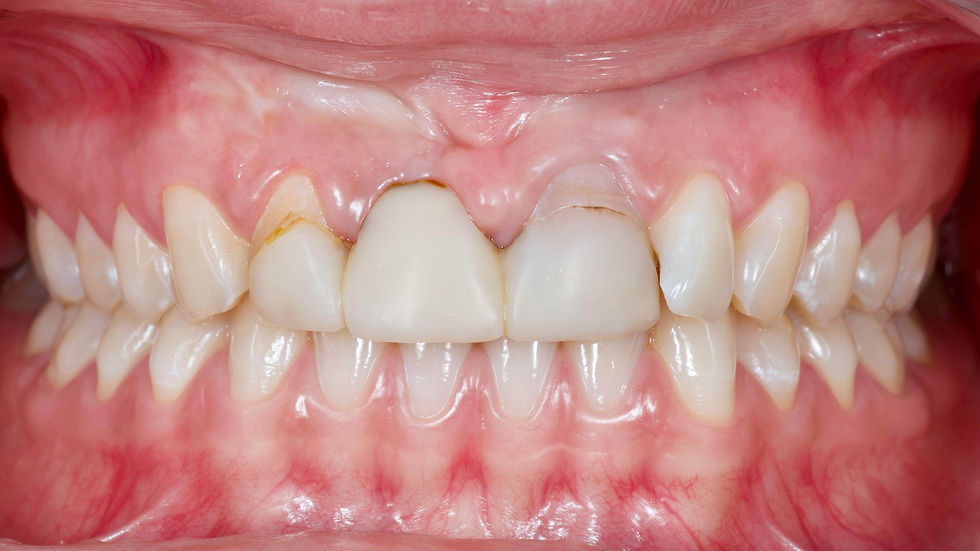

The comparison between the intraoral pictures and the bone volumes revealed at the CBCT examination highlights the severe vestibular bone atrophy and the irregularity of the marginal crest.

The comparison between the clinical picture and the diagnostic wax-up shows the ideal dental profiles and volumes providing indications on the quantity of volume that is necessary to recreate to reach the aesthetic goals.